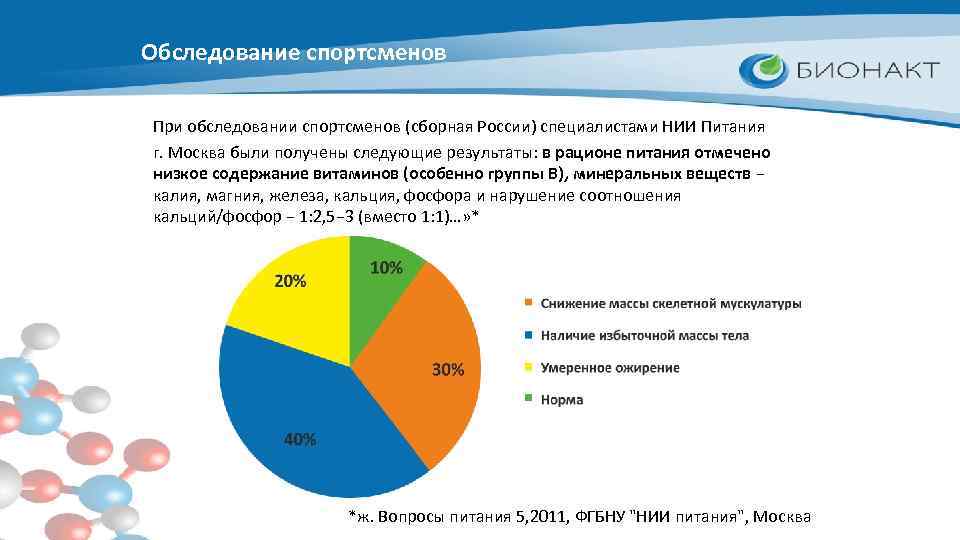

Обследование спортсменов При обследовании спортсменов (сборная России) специалистами НИИ Питания г. Москва были получены следующие результаты: в рационе питания отмечено низкое содержание витаминов (особенно группы В), минеральных веществ − калия, магния, железа, кальция, фосфора и нарушение соотношения кальций/фосфор − 1: 2, 5− 3 (вместо 1: 1)…» * *ж. Вопросы питания 5, 2011, ФГБНУ "НИИ питания", Москва

Обследование спортсменов По данным НИИ Питания Г. Москва до 35% профессиональных спортсменов и до 65% спортсменов, закончивших спортивную карьеру, страдают различными нарушениями обмена веществ* *ж. Вопросы питания 5, 2011, ФГБНУ "НИИ питания", Москва